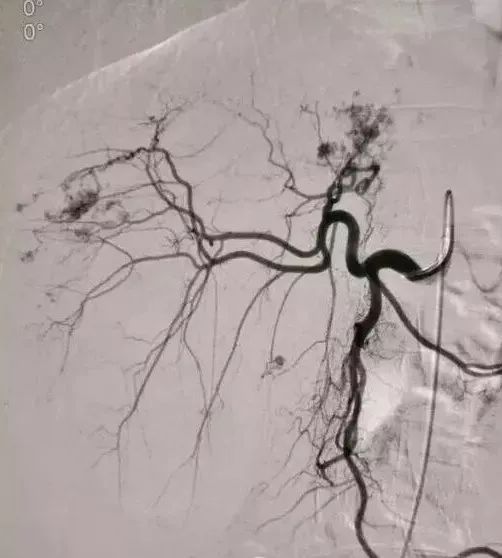

亦称介入性血管造影学(Interventional angiography),是指在诊断性血管造影的同时,自导管向血管管腔内注射药物或某些物质或施行某种措施,以达治疗目的。常用血管介入技术有三种。

2、经导管血管栓塞法(Transcatheter embolization)

经原血管造影的导管或特制的导管,将栓塞物送至靶血管内,一是治疗内出血如外伤性脏器出血、溃疡病、肿瘤或原因未明的脏器出血。另一是用栓塞法治疗肿瘤,因肿瘤循环部分或全部被栓塞物阻断,以达控制肿瘤之生长,或作为手术切除的一种治疗手段;亦可用于非手术脏器切除,例如注射栓塞物质于脾动脉分支内,即部分性脾栓塞,以治疗脾功亢进,同时不影响脾脏的免疫功能。

(3)应用栓塞材料,钢圈,内支架治疗动脉瘤、AVM、动静脉瘘,血管性出血。

(1)选择性肿瘤供血动脉灌注化疗+栓塞治疗恶性肿瘤。